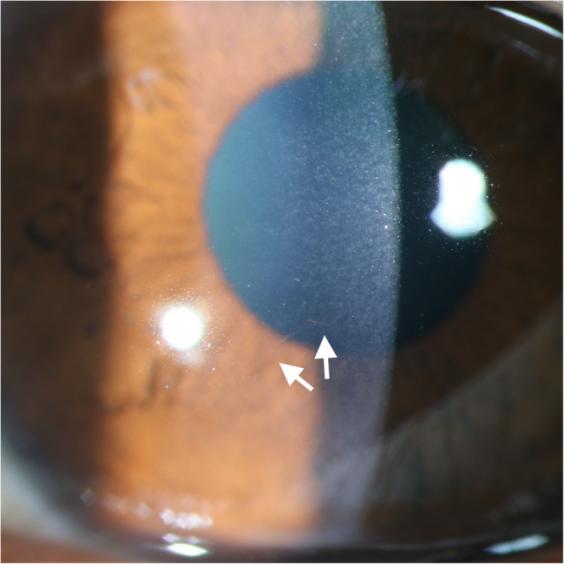

在当地医院的初步检查显示,双侧角膜点状上皮缺陷和结膜充血,右眼更严重。右眼显示角膜基质和内皮水肿,特别是在下部区域(图1)。右眼的未矫正视力为0.04,左眼为0.25(在这种情况下,所有视力测量都是使用标准对数视力表进行的),右眼视力仍然无法用眼镜矫正。眼压和前房检查双侧正常。还发现了影响1%面部表面积的II级冻伤,包括眼睑起泡。II级损伤代表水疱形成:全层皮肤冻结、红斑、严重水肿、透明水疱、脱皮和形成黑色焦痂。

图1 裂隙灯检查显示右眼角膜基质和内皮水肿,主要影响下部区域(马拉松后3天)

到暴露后第三周,右眼水肿和浅表染色几乎完全消失。双眼未矫正视力提高到0.3,对眼镜矫正有反应。之前的治疗方案又继续了一周。然而,在角膜下部的内皮水平上发现了一个1毫米的丝状疤痕(图3)。前节OCT检查证实了这一发现,即内皮细胞高信号强度增厚的焦点区域(图4)。接触后一个月和两个月的电话随访证实,眼部状况稳定,右眼内皮丝状瘢痕持续存在。

图3 角膜水肿和表面染色接近完全消退,角膜下段内皮水平持续存在1mm丝状瘢痕(白色箭头)(马拉松后3周)